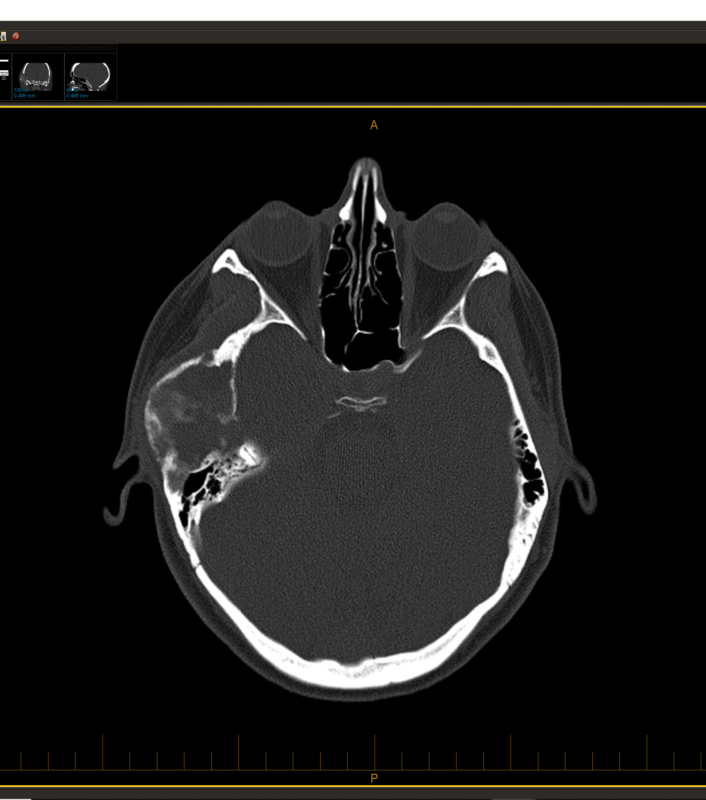

By July 2019, I had had enough. I sought out a doctor who would listen and order CT scans — my primary doctor thankfully was willing to investigate. While it appears that they may have confused my chart with someone else (the nurse at first told me I have nasal polyps, which I do NOT have), it was clear to me that I had a large tumor in my skull. This is part of being your own best advocate as a patient — go pick up your test results and look at them yourself, like I did. I learned a LOT about radiology analysis that week, comparing my scans with others on educational sites.

With my husband Don supporting me (and his Entrepreneurs Organization connections getting me in touch with the best skull-based surgeon in the state, who had arrived in OK only a few months before my surgery), I saw several specialists ranging from neurosurgery to orofacial and plastic surgery to ear nose throat surgery. My surgical team of 3 planned out the delicate procedure, concerned that I might lose hearing in my right ear if the tumor impinged on the ear canal, perhaps end up with severe paralysis in my face if the trigeminal nerves were too entangled, and maybe my jaw would need replacing on that right side. At the time, the surgeons thought I might have a hemangioma. But based on the radiology scans, I wondered if it was FD (fibrous dysplasia), due to the shattered glass-like look.

Diagnosis: Monostotic Craniofacial Fibrous Dysplasia — non-cancerous, spongey tumor that ate my cheekbone and was 1 mm from making me deaf in my right ear.